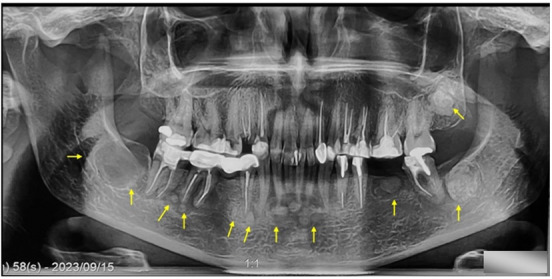

Cemento-osseous dysplasia (COD) is classified, by the World Health Organization as a benign fibro-osseous lesion related to the tooth and periapical area of the jaws and is considered as a benign reactive process appearing from the apical periodontium in close relation with the apices of teeth. Usually, it is asymptomatic, discovered accidentally, and affecting particularly middle-aged African women. There are four subtypes distinguished of the lesion: periapical (PCOD), focal (FCOD), florid (FLCOD) and familial florid cemento-osseous dysplasia (FFLCOD). Pseudocysts found in the jaws go by various names, including solitary bone cyst, traumatic bone cyst, or simple bone cyst (SBC). These two pathologies have been reported separately; however, their co-occurrence remains rare and the first case of FLCOD with co-occurrence of SBC was reported by Melrose et al. in 1976 and later a few cases been reported in the literature. The aim of this report is to describe a case of a 46-year-old oriental female diagnosed with FLCOD with co-occurrence of SBC. Under local analgesia, a surgical exploration of the cyst was performed. In addition, a biopsy with a trephine was done in the region of missing right first mandibular molar. Based on the patient clinical, radiographic, and histological findings, a diagnosis of FLCOD was made in co-occurrence with a mandibular SBC. An examination of another female family member unveils a distinctive case, and the familial factor has been ruled out. No further treatment was planned and only follow-up was suggested.

根据世界卫生组织的分类,牙骨质发育不良(COD)是一种与牙齿和颌骨根尖周围有关的良性纤维骨病变,被认为是一种良性反应性过程,出现在与牙齿根尖密切相关的根尖牙周。它通常无症状,偶然发现,主要影响中年非洲妇女。这种病变可分为四种亚型:根尖周型(PCOD)、局灶型(FCOD)、花斑型(FLCOD)和家族性花斑牙骨质发育不良型(FFLCOD)。颌骨中发现的假性囊肿有多种名称,包括单发性骨囊肿、创伤性骨囊肿或单纯性骨囊肿(SBC)。1976年,Melrose等人报告了第一例同时伴有SBC的FLCOD病例,后来又有一些病例在文献中出现。本报告旨在描述一例被诊断为 FLCOD 并发 SBC 的 46 岁东方女性病例。在局部镇痛的情况下,对囊肿进行了手术探查。此外,还在右下颌第一臼齿缺失区域进行了穿刺活检。根据患者的临床、影像学和组织学检查结果,诊断为下颌SBC同时伴有FLCOD。对另一名女性家庭成员的检查发现了一个独特的病例,并排除了家族因素。没有进一步的治疗计划,只建议进行随访。